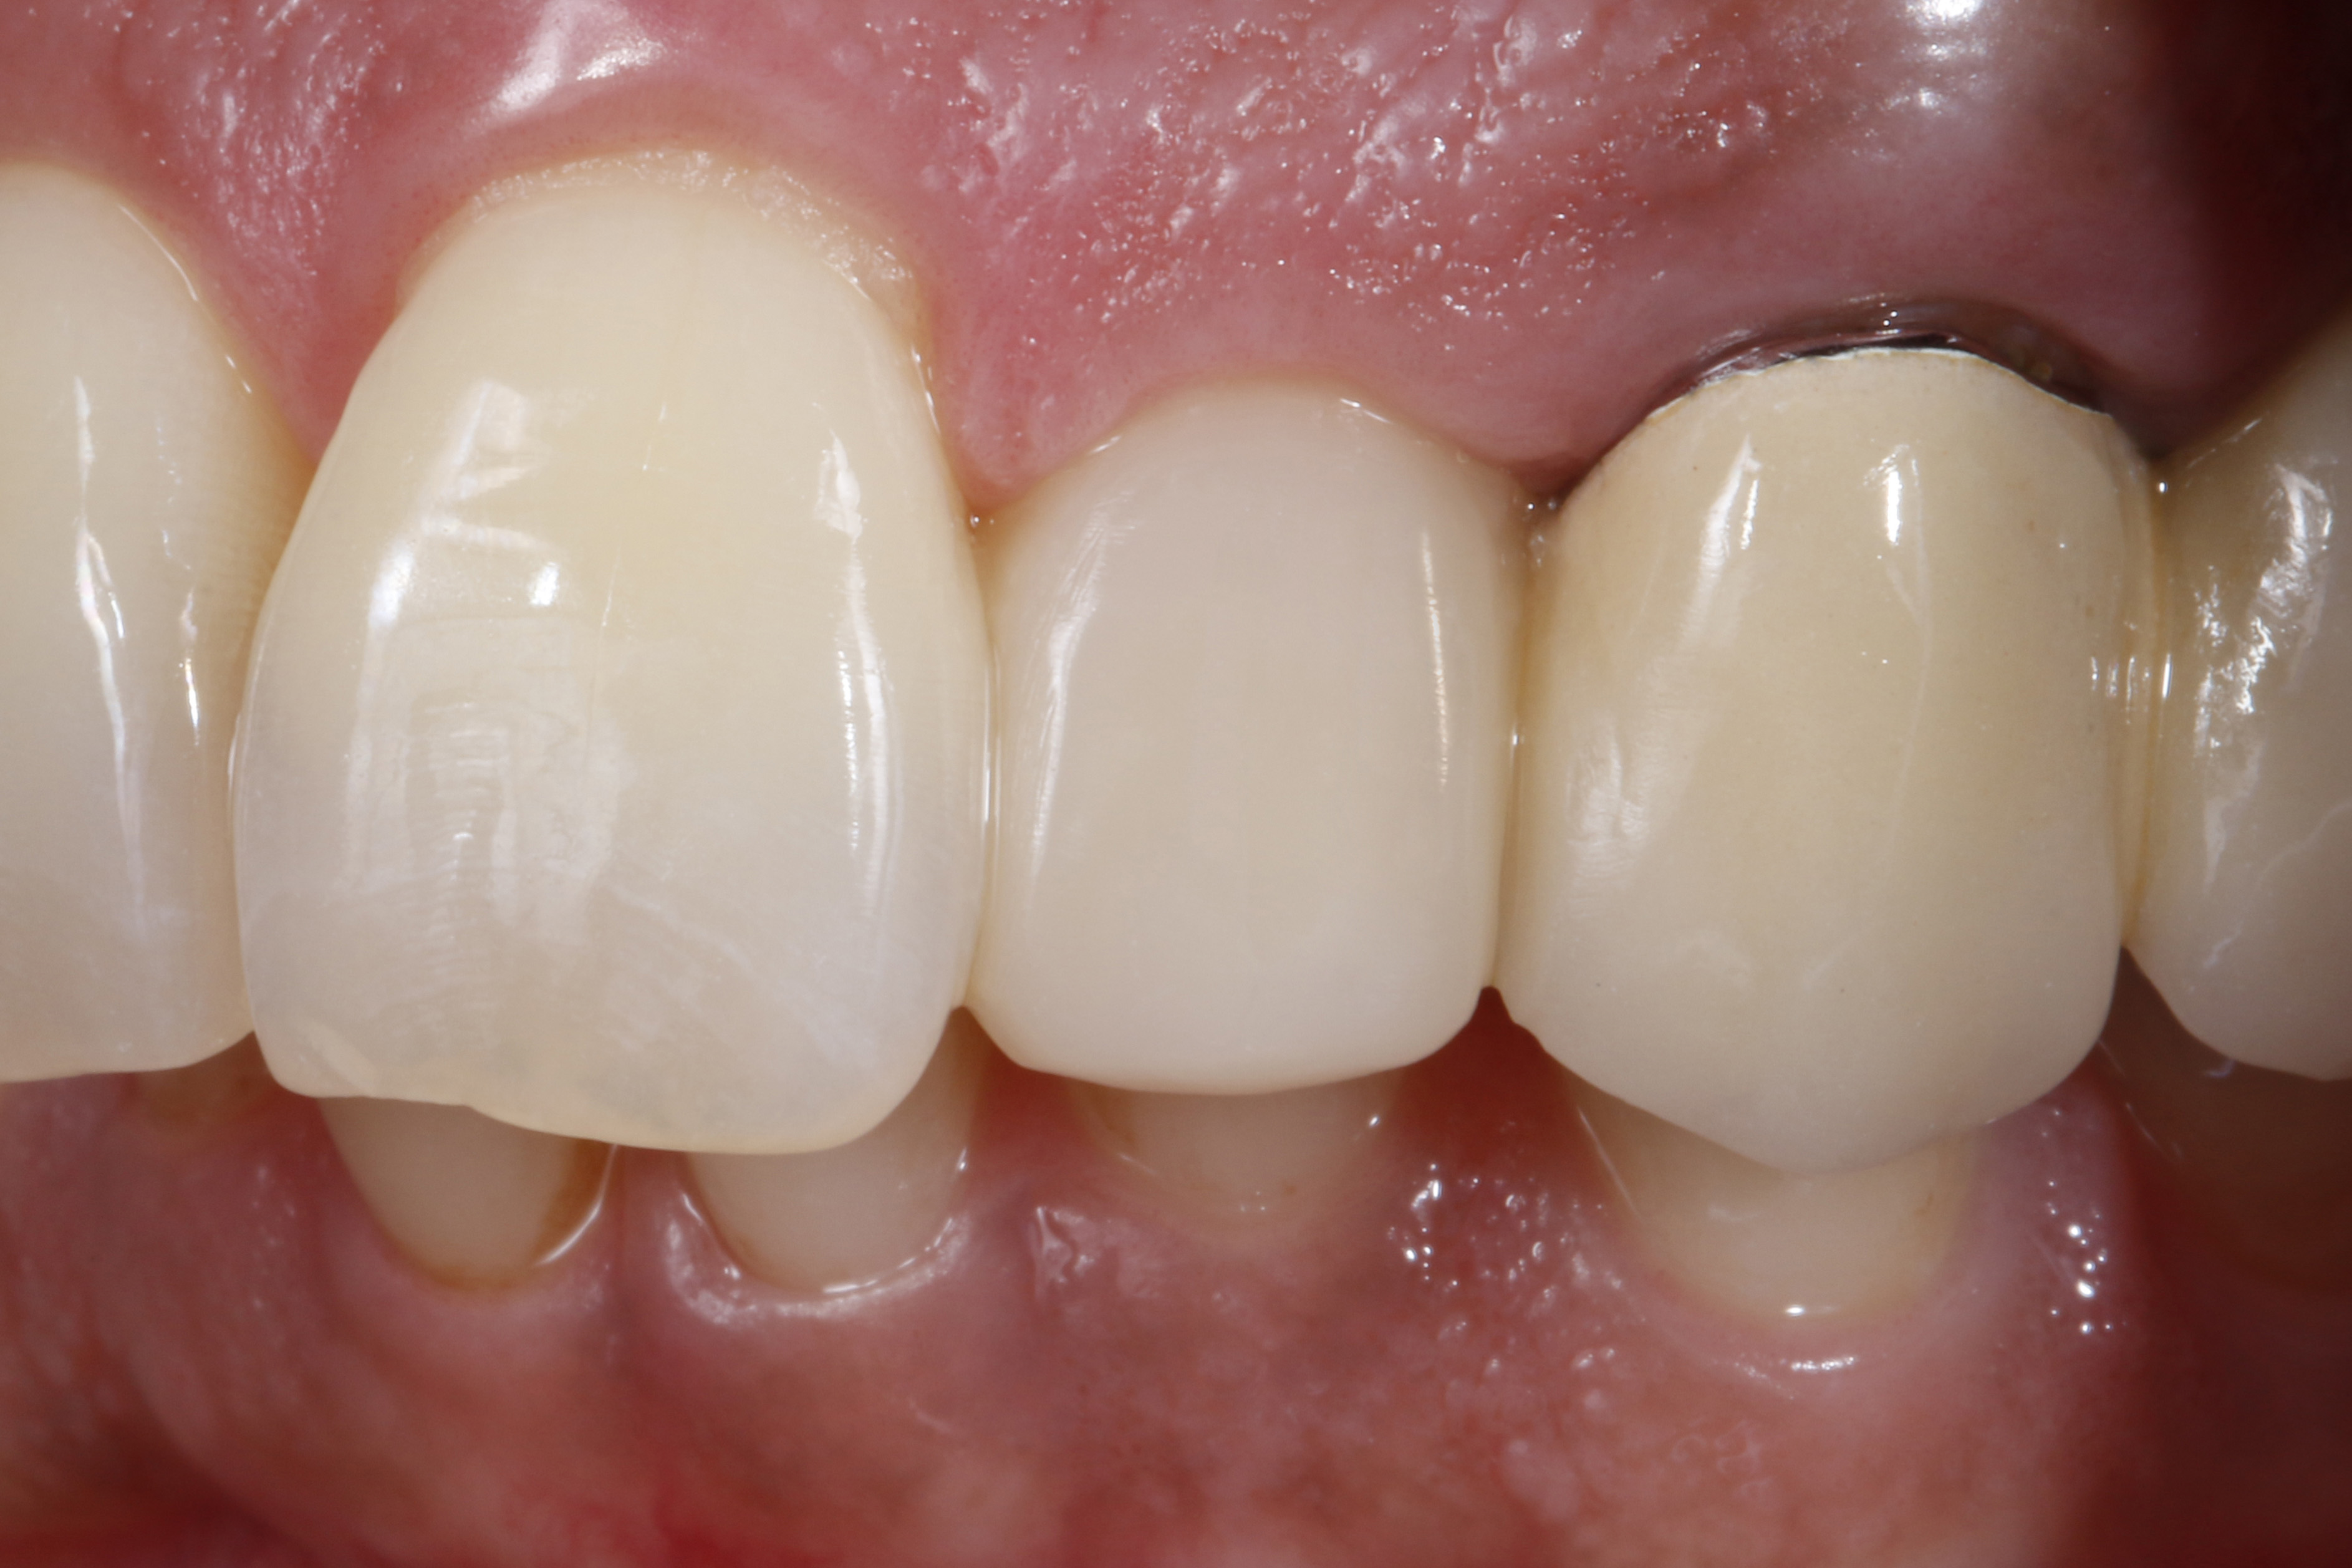

Do naszego gabinetu stomatologicznego zgłosiła się 60-letnia pacjentka z prośbą o lepsze optyczne ustawienie w łuku zębowym lewego bocznego siekacza szczęki, który jest wyraźnie położony podniebiennie w stosunku do lewego siekacza centralnego (ryc. 1 i 2).

Oprócz samego zęba, pacjentce szczególnie przeszkadzał fakt, że ząb wydawał się znacznie ciemniejszy w uśmiechu w porównaniu z lewym siekaczem centralnym i koroną PFM na lewym kle. Ząb bezzwłocznie zareagował nadwrażliwością na test na zimno, nie wykazał przy tym nieprawidłowości w teście opukiwania. Po zapoznaniu się z możliwymi alternatywami leczenia i ich kosztami, pacjentka zdecydowała się na licówkę bezpośrednią z użyciem uniwersalnego kompozytu GrandioSO Unlimited (VOCO GmbH, Cuxhaven).

Ryc. 1, 2. Sytuacja wyjściowa: lewy siekacz boczny jest ustawiony wyraźnie podniebiennie w stosunku do zębów sąsiednich. To przeszkadza pacjentce, który chciałaby uzyskać lepszą integrację wizualną z łukiem zębowym.

Bezpośrednią licówkę kompozytową wykończono stosując narzędzia obrotowe i krążki ścierne. Gładką i błyszczącą powierzchnię rekonstrukcji uzyskano za pomocą gumek do kompozytów (Diacomp Twist, EVE Ernst Vetter GmbH, Keltern) (ryc. 20). Efektem zastosowania licówki jest wargowe przesunięcie siekacza bocznego, co znacznie poprawiło jego pozycję w łuku zębowym (ryc. 21). Na koniec na ząb nałożono lakier fluorkowy (Bifluorid 10, VOCO GmbH, Cuxhaven), stosując kulki z gąbki.

Ryc. 20, 21. Efekt końcowy.